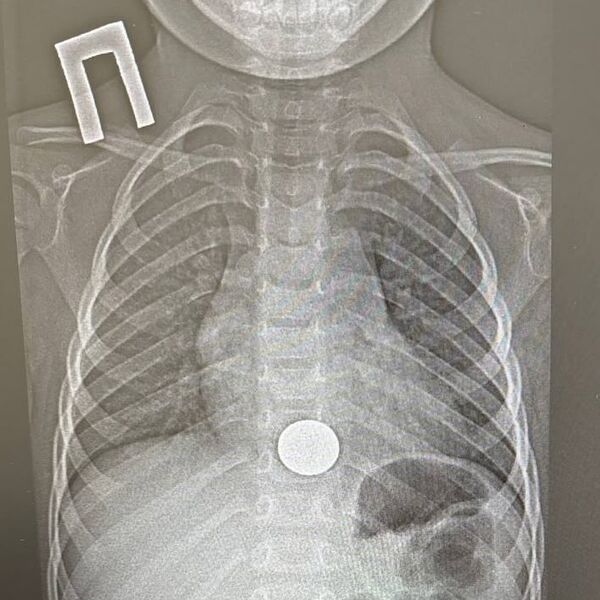

Двухлетний ребенок проглотил монету и попал в больницу в Татарстане

В Татарстане спасли двухлетнего ребенка, проглотившего монету

В Татарстане ребенок проглотил монету и попал в больницу. Об этом сообщает пресс-служба ГАУЗ НДРБ с ПЦ.

Инцидент произошел 15 декабря. Малолетний взял у старшего брата монету, чтобы поиграть с ней, и случайно ее проглотил. Ребенок сразу рассказал об этом родителям, и мать оперативно доставила его в больницу. Мальчик жаловался на боль за грудиной.

Пациенту провели рентген и обнаружили у него инородное тело в пищеводе, детский врач выполнил эндоскопическое удаление монетки. Вся процедура заняла около минуты.